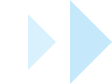

AI Crown

Intelligently generates dental crowns, auto-filling undercuts with meticulous precision.